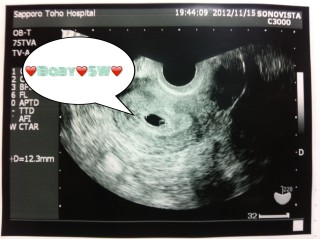

クリスマスの朝に検査薬を試したら陽性でその日のうちに病院へ。 まだ早いから見えないかもね~とおじいちゃん先生に言われ、 本当に最初の数秒は何も写らなかったのですが、 いきなり真ん中にパッと現れてくれました。

見えたね~よかったね~と言われ、本当にいたんだ。と 喜びよりも驚きで呆然としてしまいました。 コウノトリではなくサンタさんが運んできた、と思いました。